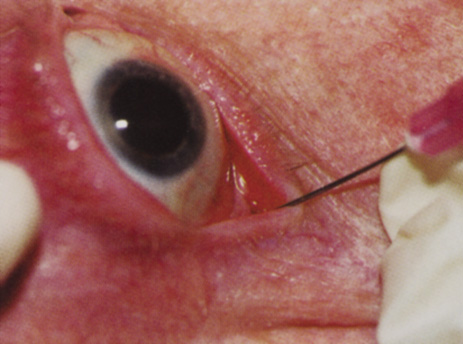

Although slit-lamp examination can give the ophthalmologist an excellent estimate of endothelial health, sometimes a formal assessment of the corneal endothelial cell density is helpful (Fig. 4). This information is most likely to be helpful in advising patients who may be at greater risk of postoperative corneal decompensation. Specifically, patients with cornea guttata, previous ocular surgery, history of blunt ocular injury,56 exfoliation syndrome,57 iridocorneal-endothelial syndromes,58 or a history of glaucoma59 are known to have reduced endothelial cell counts. Patients with a history of acute angle closure are at particular risk because each episode of elevated intraocular pressure can damage endothelial cells.60

There are qualitative and quantitative methods for endothelial cell evaluation. Cell density can be measured directly with an endothelial cell camera. The surgeon also should view the photograph and qualitatively estimate the regularity of the endothelial cell mosaic. Some instruments calculate a coefficient of variability and percent of hexagonal cells.

When an endothelial cell camera is not available, qualitative assessment of count and cell morphology can be accomplished at the slit-lamp using a technique called specular reflection.61 The ophthalmologist focuses a narrow parallelepiped on the corneal epithelium, directing the beam at the periapical cornea from a 45-degree angle. The slit beam is moved slowly from side to side until the bright corneal reflex strikes the examiner's view from the epithelial surface reflection (first Purkinje-Sanson image). On high magnification, the examiner should focus on the endothelial surface just next to the bright reflex. The image of the endothelial mosaic will come into view. The surgeon can make a qualitative assessment of the cell density and degree of regularity. With practice, these estimates can be surprisingly accurate.

The implications of a reduced endothelial cell count are primarily prognostic and can provide the surgeon with more information to help counsel the patient about the risk of corneal decompensation with cataract surgery. Gentle phacoemulsification without triple procedure is recommended when cornea is clear and compact, given that a significant number of patients may be able to avoid a corneal transplant despite uncountable cell densities. However, these patients should be advised that they may be at an increased risk of requiring a corneal transplant.